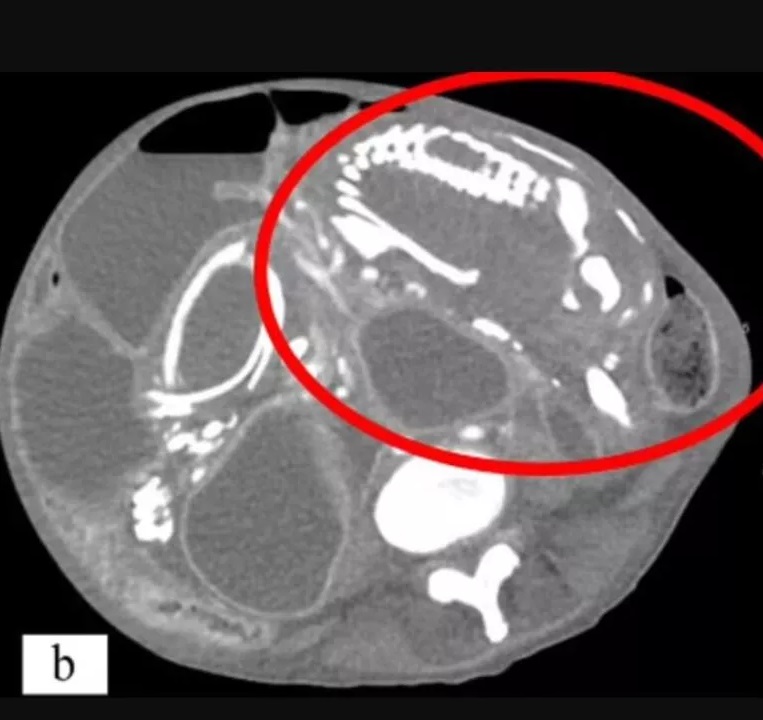

Doktorlar yaptıkları taramalarda kadının karnında 15-20 cm büyüklüğünde bir iskelet olduğunu keşfettiler ve kadına bu kitlenin alınması gerektiğini söylediler. Geçmişte yaşadığı olaylardan dolayı durumunun bir 'lanetten' kaynaklandığını iddia eden kadın ameliyat olmayı reddetti ve sadece antibiyotik almaya ikna oldu.

Anne karnındaki ölü fetüsü yabancı bir madde olarak algılayan vücut koruma kalkanını açar ve ölü bebeğin anneye zarar vermemesi için zamanla kireçlenmeye (kalsifikasyon) başlar. Annenin vücut savunma mekanizması tarafından gerçekleştirilen bu olay sonunda anne karnındaki fetüs zamanla taşlaşır.